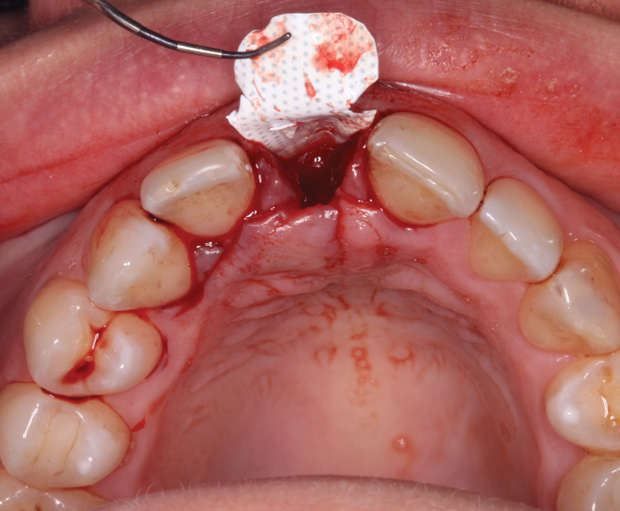

A 33-year-old woman presented with a buccal fistula at the apex of No. 8, and there was an 8-mm mid-buccal probing depth (Figure 1). The tooth had been treated multiple times by an endodontist. Based on the tooth's dental history, mobility, and its poor endodontic and periodontal prognosis, it was deemed hopeless and scheduled for extraction (Figure 2).

The right central incisor was removed atraumatically (Figure 3) without elevating a buccal flap. The presence of the buccal bone dehiscence was confirmed with the use of a periodontal probe. Measurements from the free gingival margin to the crest of the buccal bone and a horizontal assessment of the defect size indicated a dehiscence that was 8-mm tall and 5-mm wide. The distance from the free gingival margin to the most apical point in the socket was 10 mm.

Fig 3. Atraumatic extraction of central incisor.

Figure 3

Fig 6. Small-particle allograft was placed in the socket.

Figure 6

Fig 7. The d-PTFE barrier was tucked under the palatal flap (3 mm).

Figure 7

Fig 8. The barrier was secured by interrupted sutures.

Figure 8